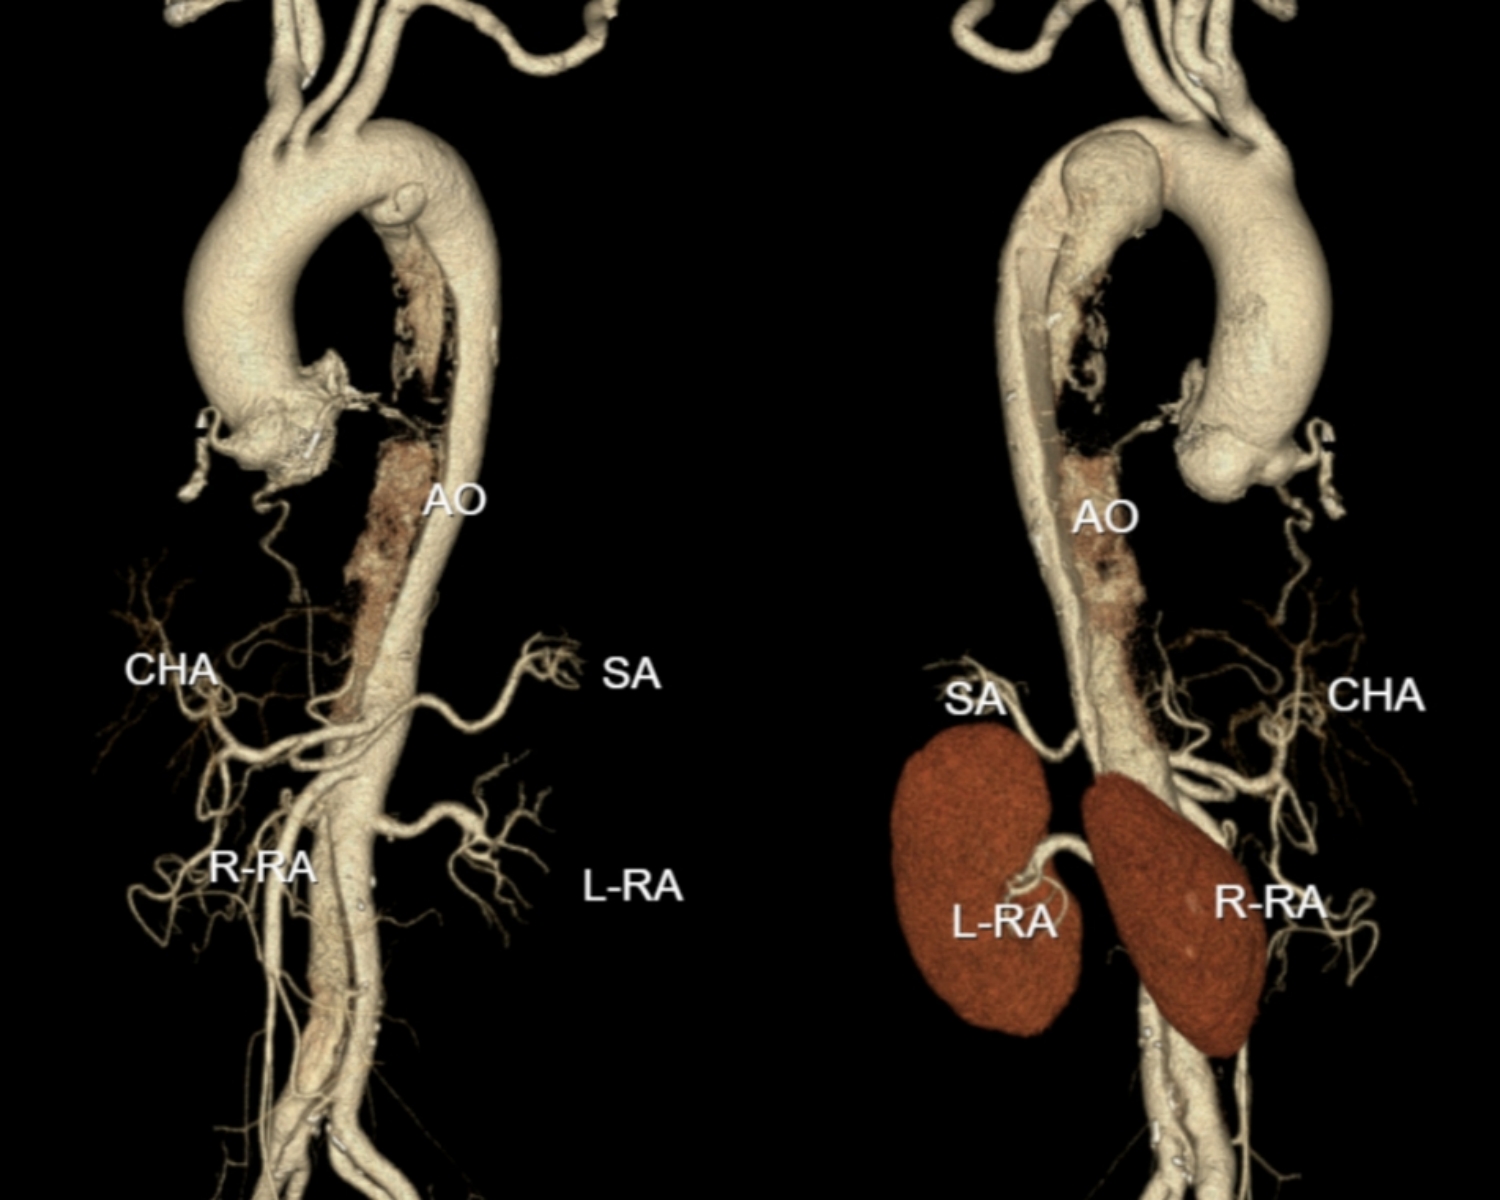

该名64岁男性患者最初因腹胀、乏力到我院消化内科就医,完善相关影像学检查后,结果提示其存在主动脉夹层。消化内科团队立即请血管与介入科进行急会诊,协助制定诊疗方案。血管与介入科唐俊主任分析该患者夹层破口接近左侧锁骨下动脉,且远端假腔内血栓形成,若不及时治疗可能有夹层逆撕影响颅脑供血,甚至出现主动脉破裂的风险。病情危重,立即安排患者转入血管与介入科进一步专科治疗,给予对症治疗后,血压、心率平稳,精神状态佳,炎症控制良好。我科立即启动多学科MDT,针对患者病情制定手术治疗方案。

唐俊主任介绍,以往遇到类似影像学表现的患者,介入微创治疗多采用“胸主动脉分支覆膜支架置入术”。但结合该患者的检查结果,其夹层虽临近左锁骨下动脉,却未累及该分支血管,团队经过综合评估,决定采用最新的“体外微孔开窗腔内微创技术”为患者治疗,并依据患者的影像学检查结果,精准规划了支架的开窗范围。